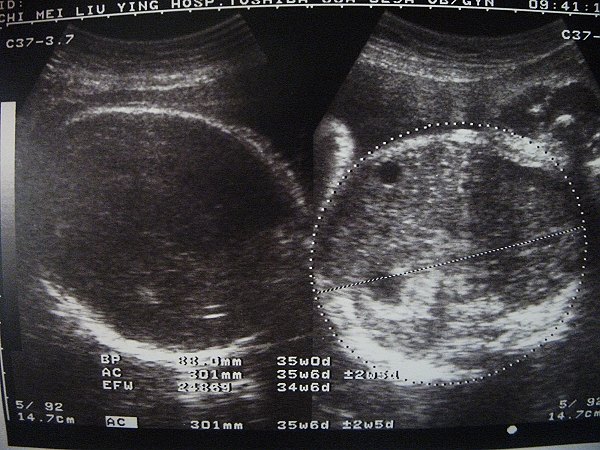

2012.05.04 34W+1

魏阿阿小姐目前的體重約2500g

比起兩週前多了600g

更可喜可賀的是~我這次體重沒增加~喔耶

2012.05.17 36W

本次體重兩週內增加了1.5KG(果然被護士警告了= =)

目前總重量是增加9KG

腰圍來到了46吋~

魏啊啊小姐這兩週只有增加300g~現在大概才2800G

醫生說羊水有點太多~要小心不要常走動~怕太早有產兆